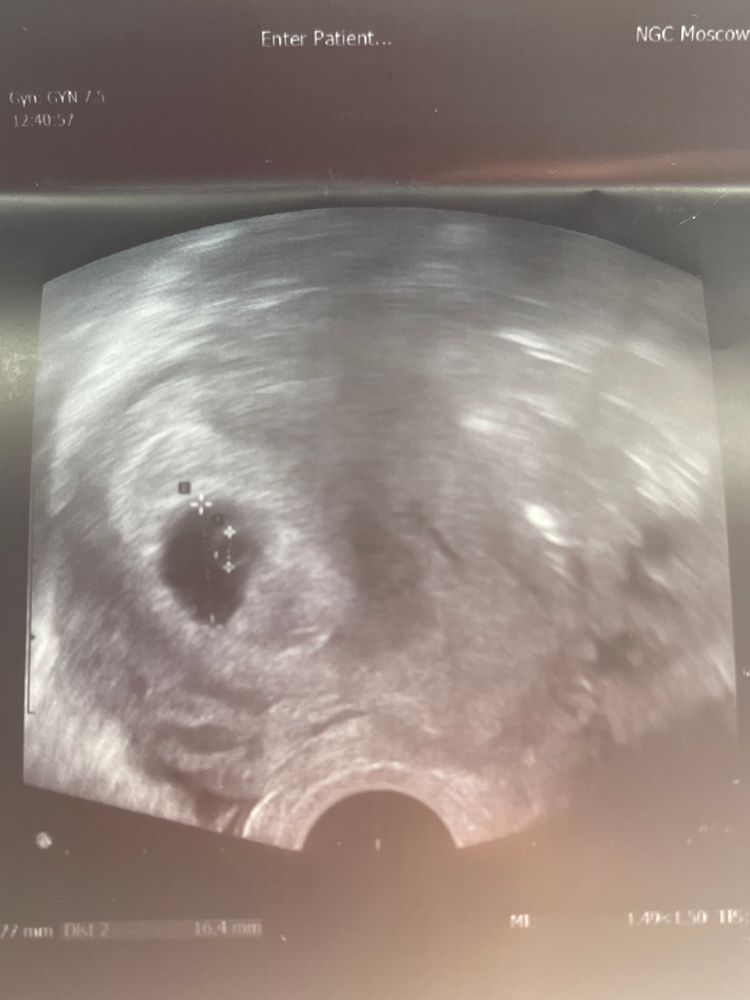

Ну в общем, у